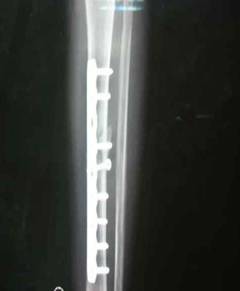

患者小林,一年前因脛腓骨骨折,小腿置入了固定鋼板。今日回院復(fù)查,患者恢復(fù)良好。管床崔醫(yī)生,已為其辦理了住院,擇期手術(shù)取內(nèi)固定鋼板。

脛腓骨內(nèi)固定鋼板